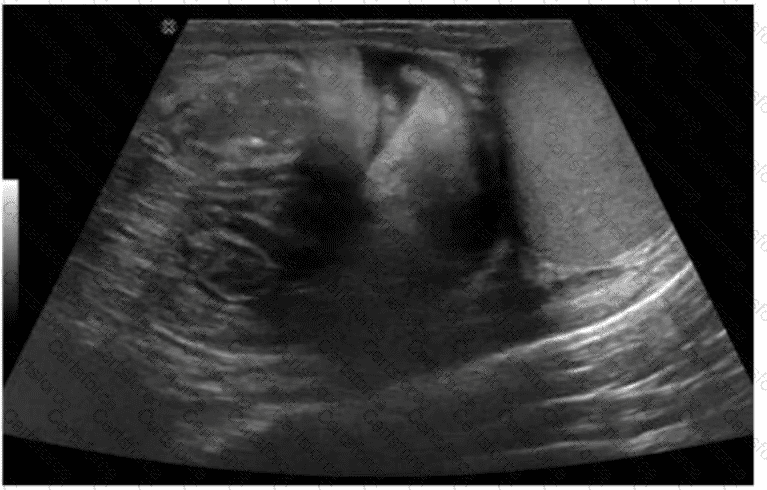

The ultrasound image demonstrates bowel loops with peristalsis visualized within the inguinal canal, which is diagnostic of an inguinal hernia—more specifically, an indirect inguinal hernia. Indirect hernias pass through the deep inguinal ring and may extend into the scrotum, appearing sonographically as bowel-containing masses adjacent to or within the scrotal sac. Peristaltic motion confirms the presence of viable bowel content.

This finding is typical in indirect inguinal hernias, which are more common in males and often congenital due to a patent processus vaginalis. The herniated bowel can be traced through the inguinal canal, as seen in this image.

D. Indirect hernia is correct. The presence of bowel with peristalsis in the inguinal canal is diagnostic.